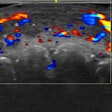

Ultrasound finds complications from cosmetic fillers